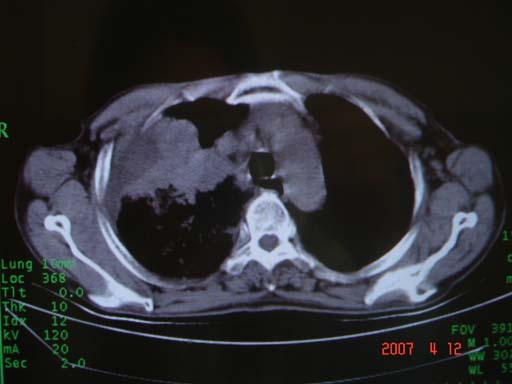

帮我 看看。男77岁咳嗽咯血2月发热2周!病人一般情况可 口痰为鲜红,有点象洗肉水(我看见他吐的痰了)

为何只有这么几幅图像?连纵隔窗都没有。但我发现上叶支气管显示不清,再加上年纪大,咯血等症状,恶性肿瘤首先得考虑。

考虑右肺新生物伴右中上肺阻塞性肺炎及含气不良,右侧胸腔积液。建议痰与纤支镜检查

考虑右侧中央型肺癌伴中上肺阻塞性肺炎、不张,胸腔积液。,建议支纤镜检查。

考虑:右上肺癌伴中上叶炎症,右侧胸腔积液。

图片不太全

根据患者老年男性,右肺上叶支气管狭窄、阻塞,伴阻塞性肺炎,考虑中心型肺癌可能性大。建议支气管镜检查

病灶局限在右肺中上叶,呈大片状实变影,内见空气支气管征,支气管分支较柔软,纵隔内未见肿大淋巴结.支持:感染性病变_1 大叶性肺炎.2 干酪性肺炎.

优先考虑右上肺干酪性肺炎并同侧中叶播散、胸腔积液。分析:右膈肌未见升高、纵隔未见明显右移,胸部各组淋巴结未见可疑肿大,中叶可见支气管铸形,肺野、肺门未见可确定肿块。

右肺上叶后段支气管中断,首先考虑中央型肺癌并右肺不张及纵隔淋巴结转移,右侧胸腔积液。